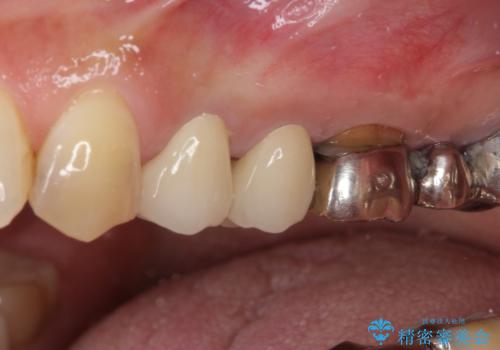

- 歯肉が退縮したためにクラウンの縁や歯根が見えてしまっていることを気にして来院された患者様です。

仮歯に変えた後にオールセラミッククラウンにて補綴することとしました。

強い咬合力や磨きすぎなどにより、歯根が見えてしまったり、金属の縁が見えてしまったりし、審美障害を引き起こすことがあります。

歯根が変色してしまうと、歯肉越しに歯根の黒い色が透けてしまうことがあり、この点についてはどうにも施しようがないため、患者様には事前のご理解いただきました。